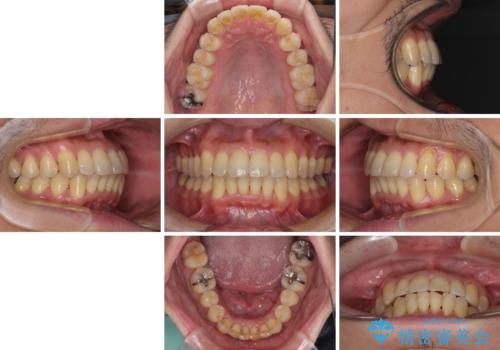

治療開始の頃は、食事や歯磨きが慣れず、装置が頻繁に脱落しましたが、2,3ヶ月ほどで慣れ、その後は1年ほどで治療を終えることができました。

前歯のデコボコ ワイヤー装置での短期間治療

- 前歯のデコボコを気にして来院された患者様です。